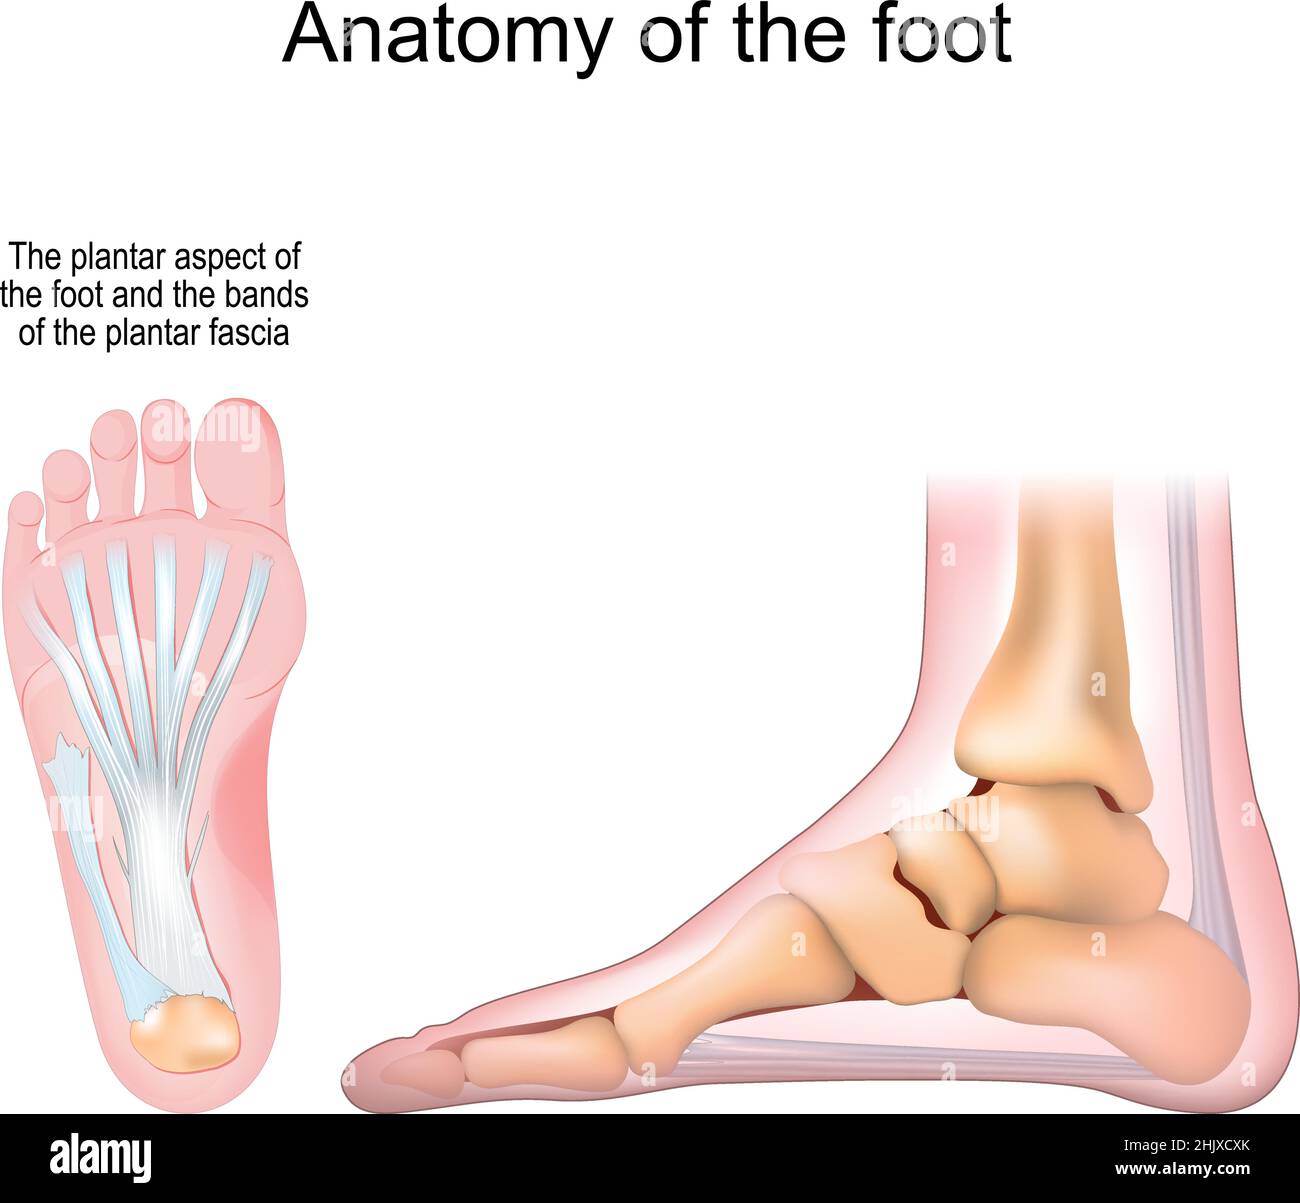

RF2HJXCXK–Anatomie du pied.OS et fascia Plantar.Illustration vectorielle réaliste. Vue de dessous et vue latérale